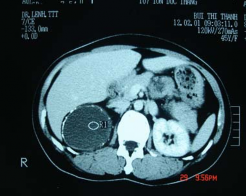

Hình 3.10: Pheochromocytome

Bệnh nhân số 38

Hình 3.11: U vỏ có kíchthước nhỏ (2cm); Bệnh nhân số 14